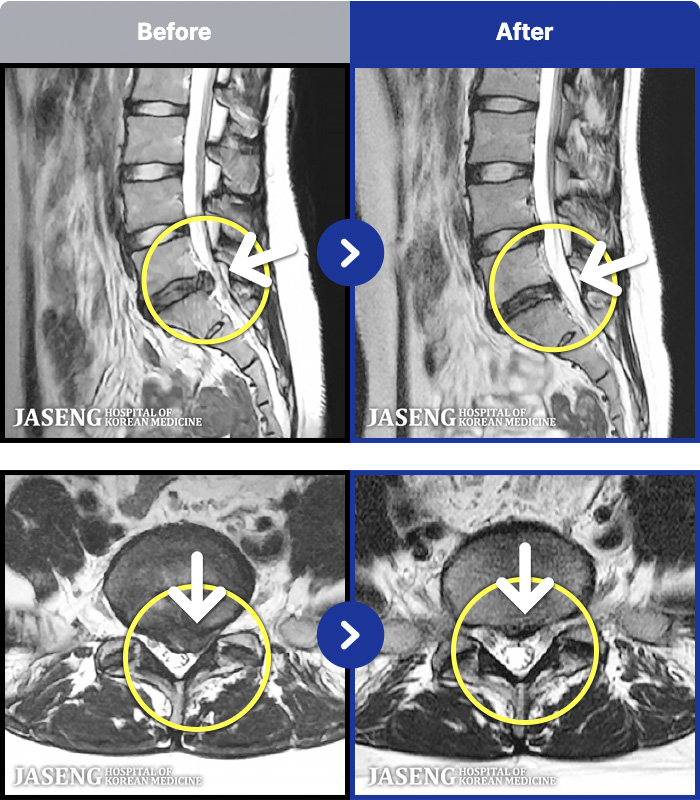

MRI ġ

1,240 MRI ũ ʸ Ȯϼ.